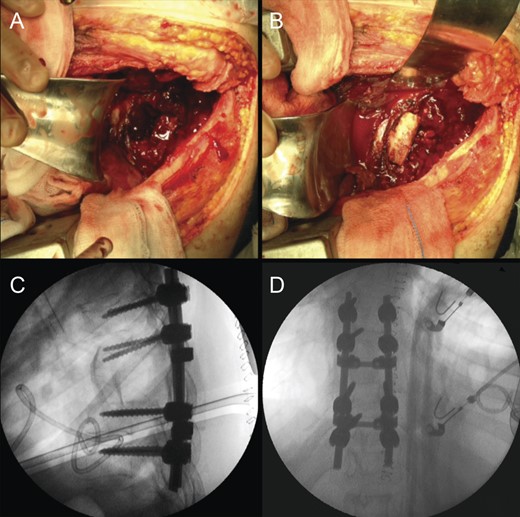

Due to the advanced stage of the lesion, with associated instability that could result in major neurologic deficits in a short time period, a total en bloc spondylectomy of T8 by a posterior-only approach was performed (Fig. 2). The operation followed the technique proposed by Tomita et al. and was complemented with anterior-column reconstruction with a titanium mesh filled with structural allograft, as well as pedicle screw instrumentation, from T6 to T10 (Fig. 3). During the procedure, the eighth dorsal nerve routes were sacrificed.

Intraoperative photographs; after total en bloc spondylectomy (A), anterior-column reconstruction was accomplished with placement of a titanium cage with structural allograft (B) and was complemented with pedicle screw-rod fixation (C). (D) Resected vertebra.